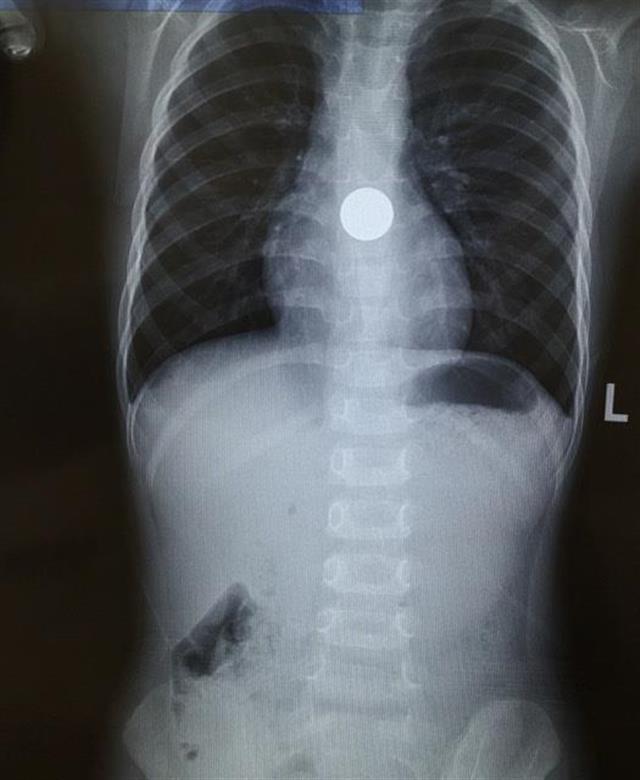

大悟3岁幼儿吞入一角硬币,辗转赴武汉取出

经过诊断,发现孩子的食道内有一个圆形金属异物,疑似硬币.